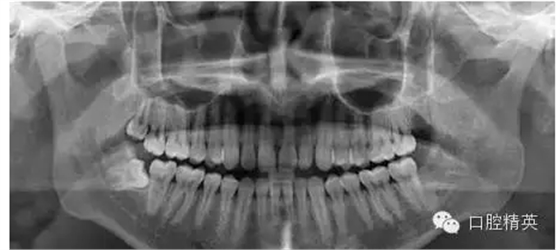

7、拔牙后全景片